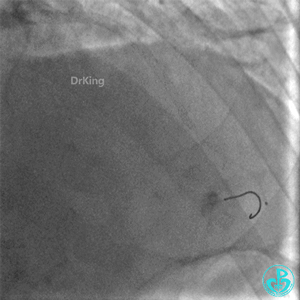

右股动脉封堵器封堵。

明胶在血管怎么降解并发症丨前降支CTO同侧逆向开通时侧支血管破裂,弹簧圈联合明胶海绵封堵_https://www.jmylbn.com_新闻资讯_第38张

病情变化

术后1小时患者诉右侧腰部疼痛、恶心、呕吐。

心率76~130次/分,血压(77~140)/(64~70)mmHg。

查体:腹部肌紧张,右侧穿刺点处有压痛。怀疑发生腹膜后血肿。

心脏超声提示少量心包积液,右下腹局限性液性区,包裹性积血不除外。